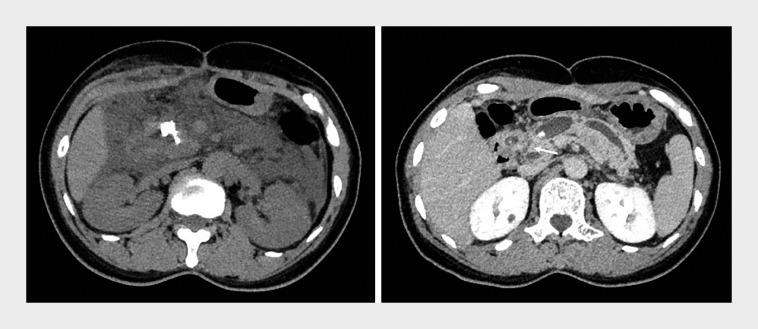

Multiple pancreaticobiliary fistulas combined with acute necrotizing pancreatitis: a rare complication of pancreatic extracorporeal shock wave lithotripsy.

摘要